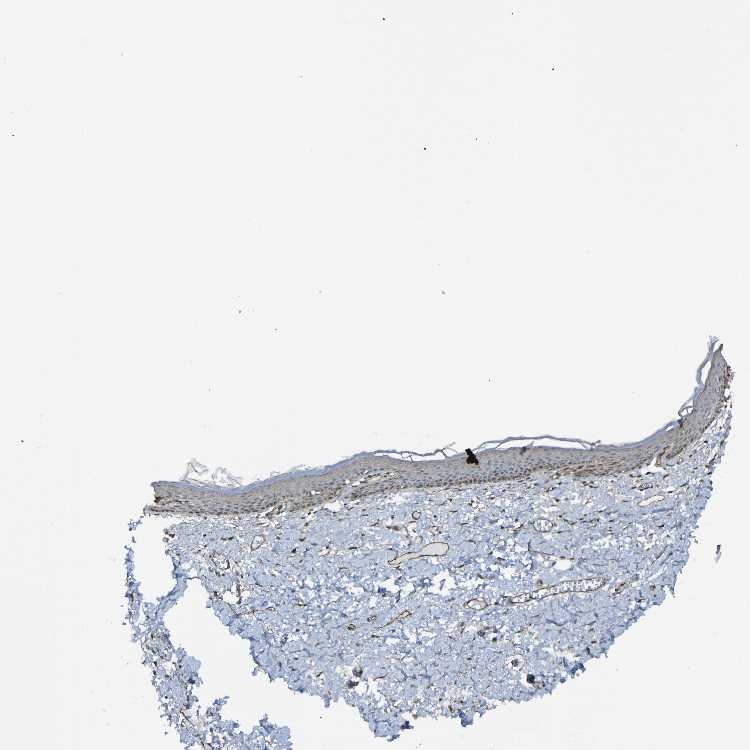

SKIN 1 - Antibody stainingi

Antibody staining in the annotated cell types in the current human tissue is reported as not detected, low, medium, or high, based on conventional immunohistochemistry profiling in selected tissues. This score is based on the combination of the staining intensity and fraction of stained cells.

Each image is clickable and will lead to virtual microscopy that enables deeper exploration of all samples and also displays staining intensity scores, fraction scores and subcellular localization as well as patient and tissue information for each sample.

Antibody HPA012530

Langerhans Low

Fibroblasts Medium

Keratinocytes Medium

Melanocytes Not detected

SKIN 2 - Antibody stainingi

Epidermal cells Not detected